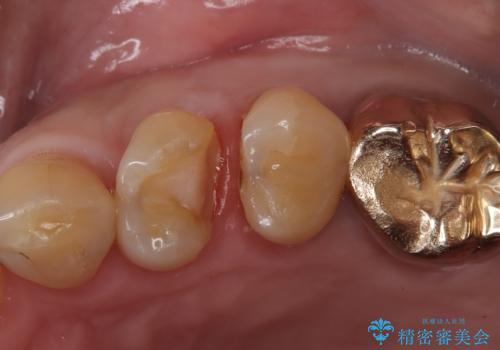

- 「フロスをしたら銀歯が取れた」を主訴に来院された患者様です。虫歯を除去した後、ゴールドインレーで治療を行いました。

隣の歯も虫歯になっており、その歯はCR(保険適応)で治療を行いました。

左上4はゴールドインレー、左上5はCR(保険適応)で治療を行いました。